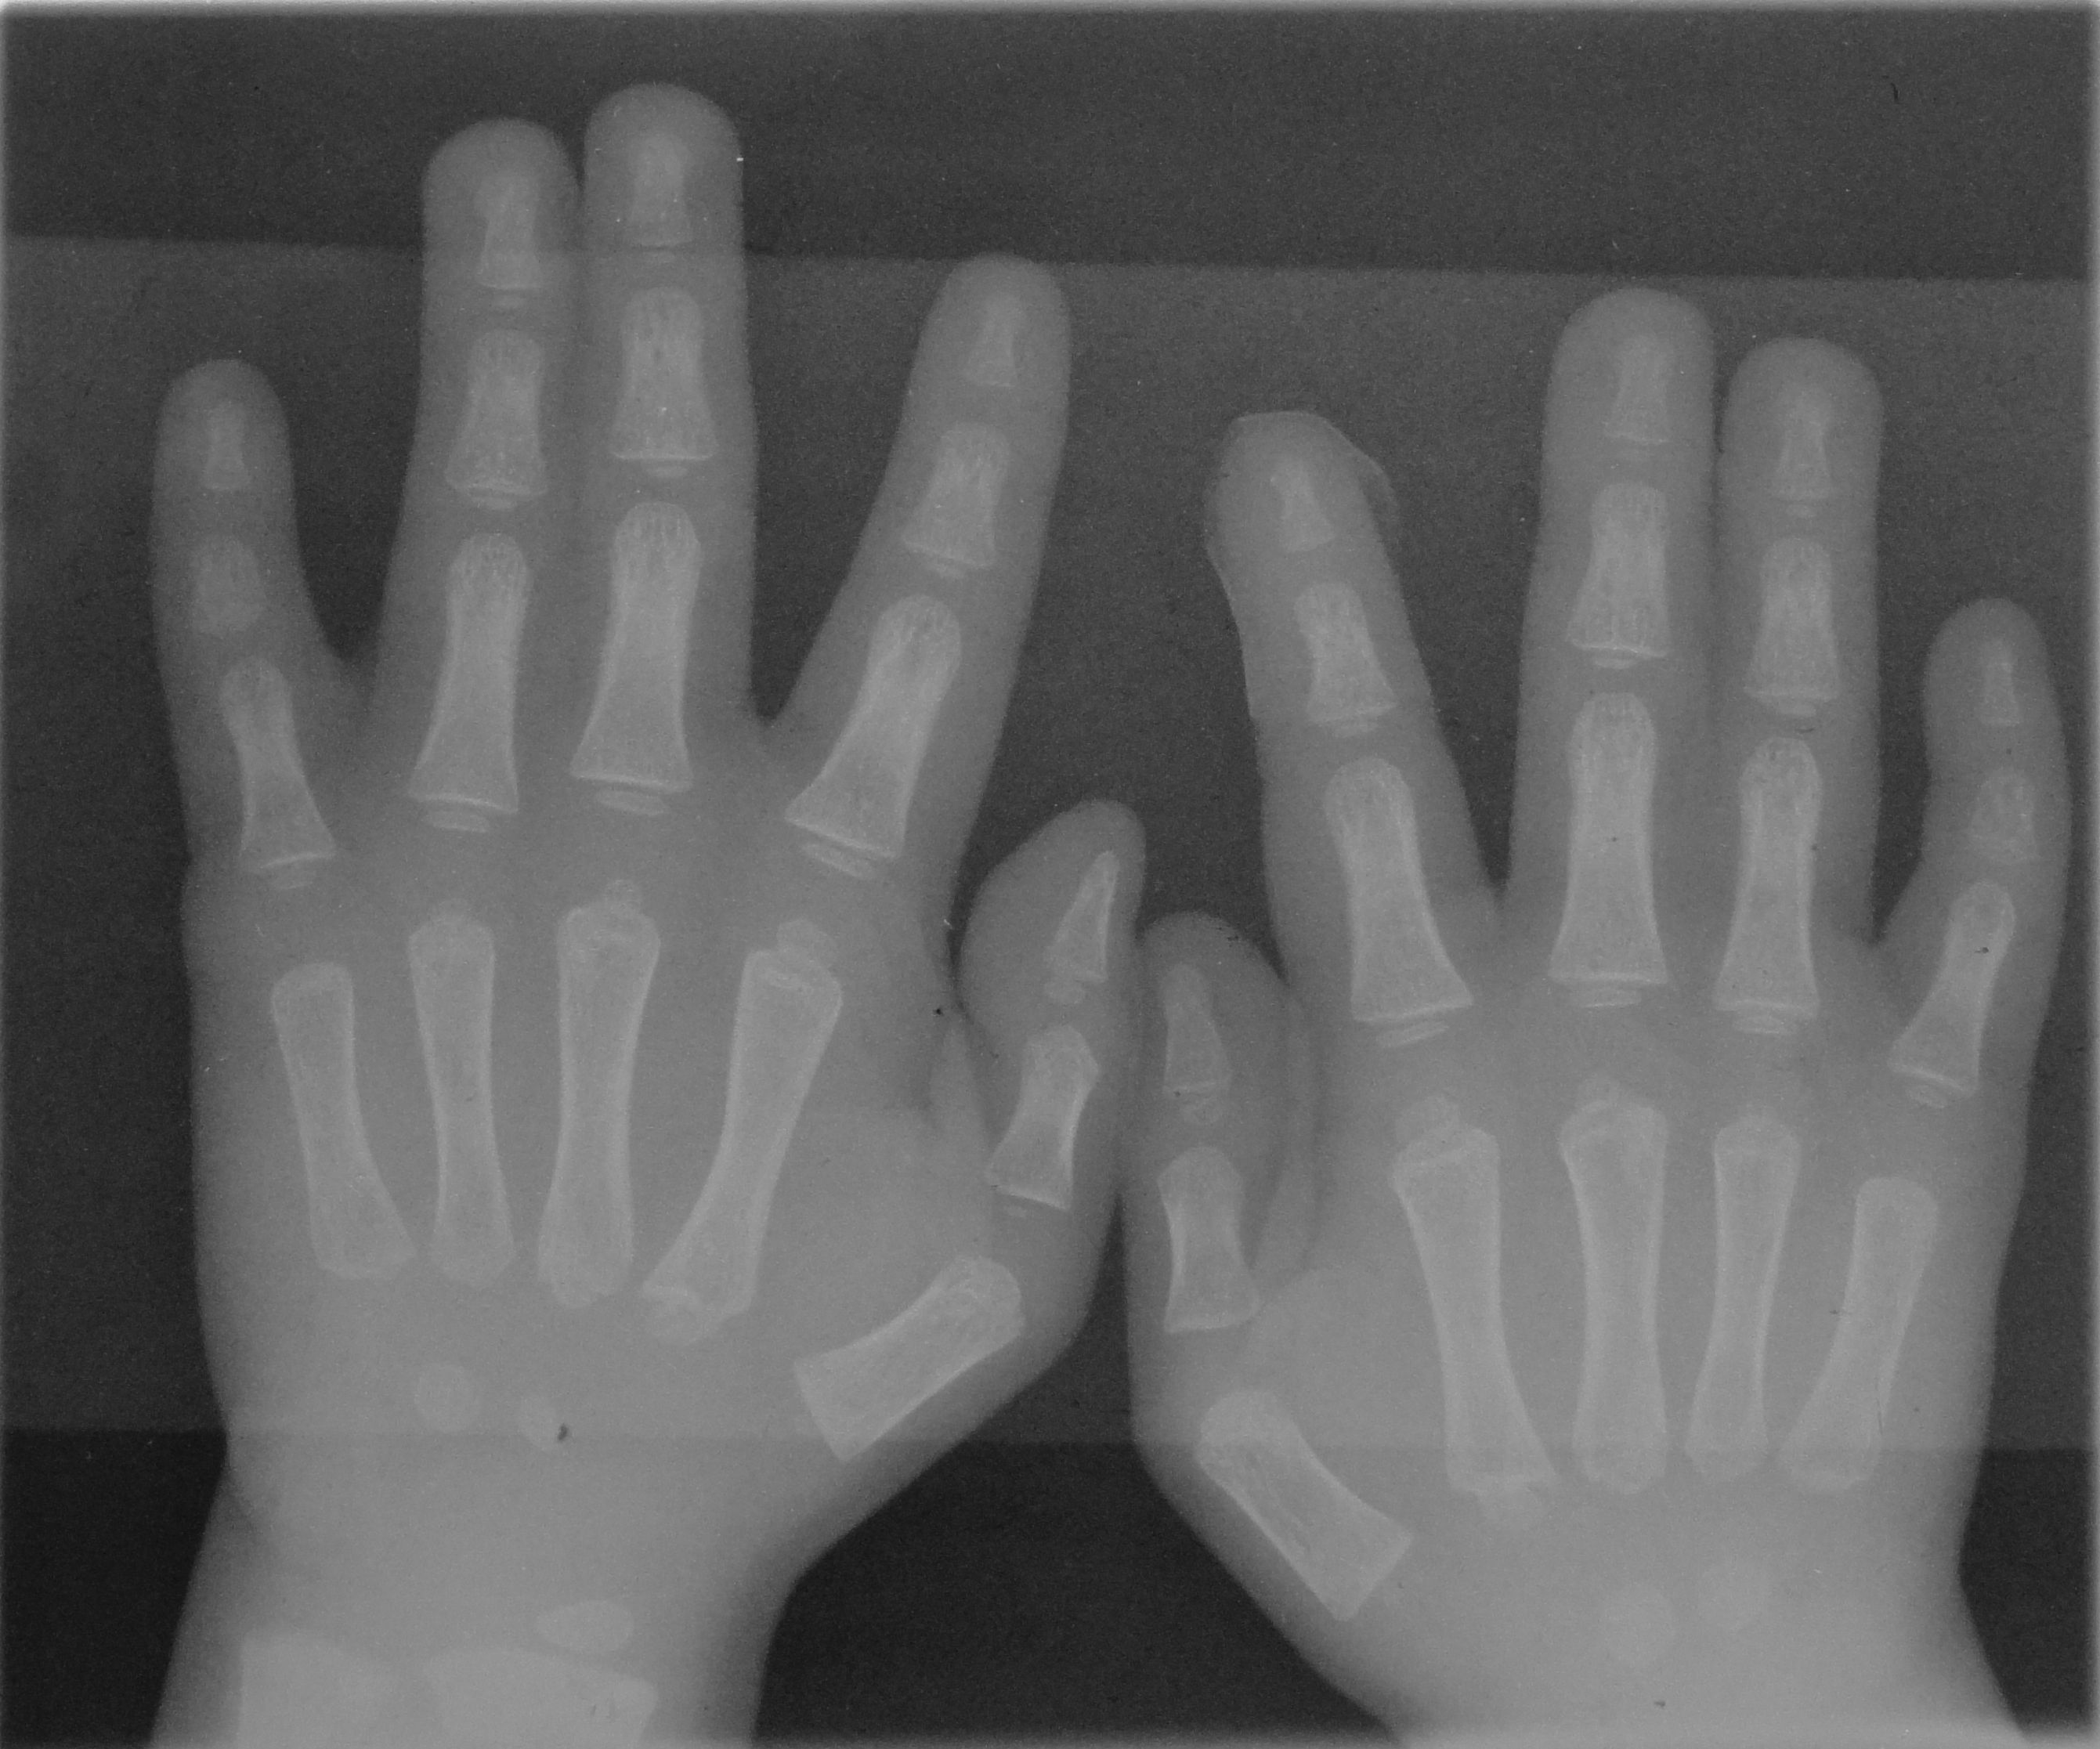

사람 손의 뼈는 과 같이 구성되어 있다. 엄지손가락은 사다리꼴에 연결되어 팔과 평행하게 한쪽에 위치한다. 손바닥에는 다섯 개의 중수골이 있으며, 각 손가락과 연결된다. 사람의 손에는 14개의 손가락뼈가 있는데, 엄지손가락에 두 개, 나머지 네 손가락에 각각 세 개씩 있다. 손가락뼈는 손톱을 지탱하는 말단 손가락뼈, 중간 손가락뼈, 근위 손가락뼈로 구성된다.종자골은 힘줄에 내장된 작고 골화된 마디로, 추가적인 지렛대를 제공하고 기초 조직의 압력을 줄여준다. 관절은 손가락뼈 사이의 손가락뼈 관절과 손가락뼈를 중수골에 연결하는 중수지 관절이다.

- 관절이 많고, 충격은 관절에 흡수되기 때문에 손가락 자체의 골절은 비교적 적지만, 손가락 삐끗 등으로 인해 손가락의 인대 손상뿐만 아니라, 손가락의 손바닥에 숨겨진 부위의 골절을 일으키는 경우가 있다. 또한 중량물에 의한 압박이 외상이 없더라도 골절을 일으키는 경우도 있으며, 구부리는 것이 가능하더라도 욱신거리는 통증이 동반될 때는 X선 촬영에 의한 관찰이 필요하다.